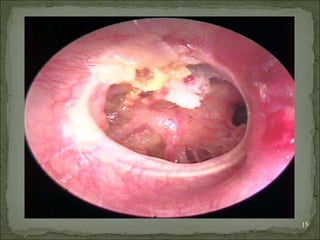

Cholesteatoma

Osteitis and granulation tissue

 Macroscopically cholesteatoma looks like a soft

pultaceous mass resembling tooth paste

contained in a sac or cholesteatoma appears to be

a rounded pearly white mass often surrounded by

friable granulation tissue from infected bone